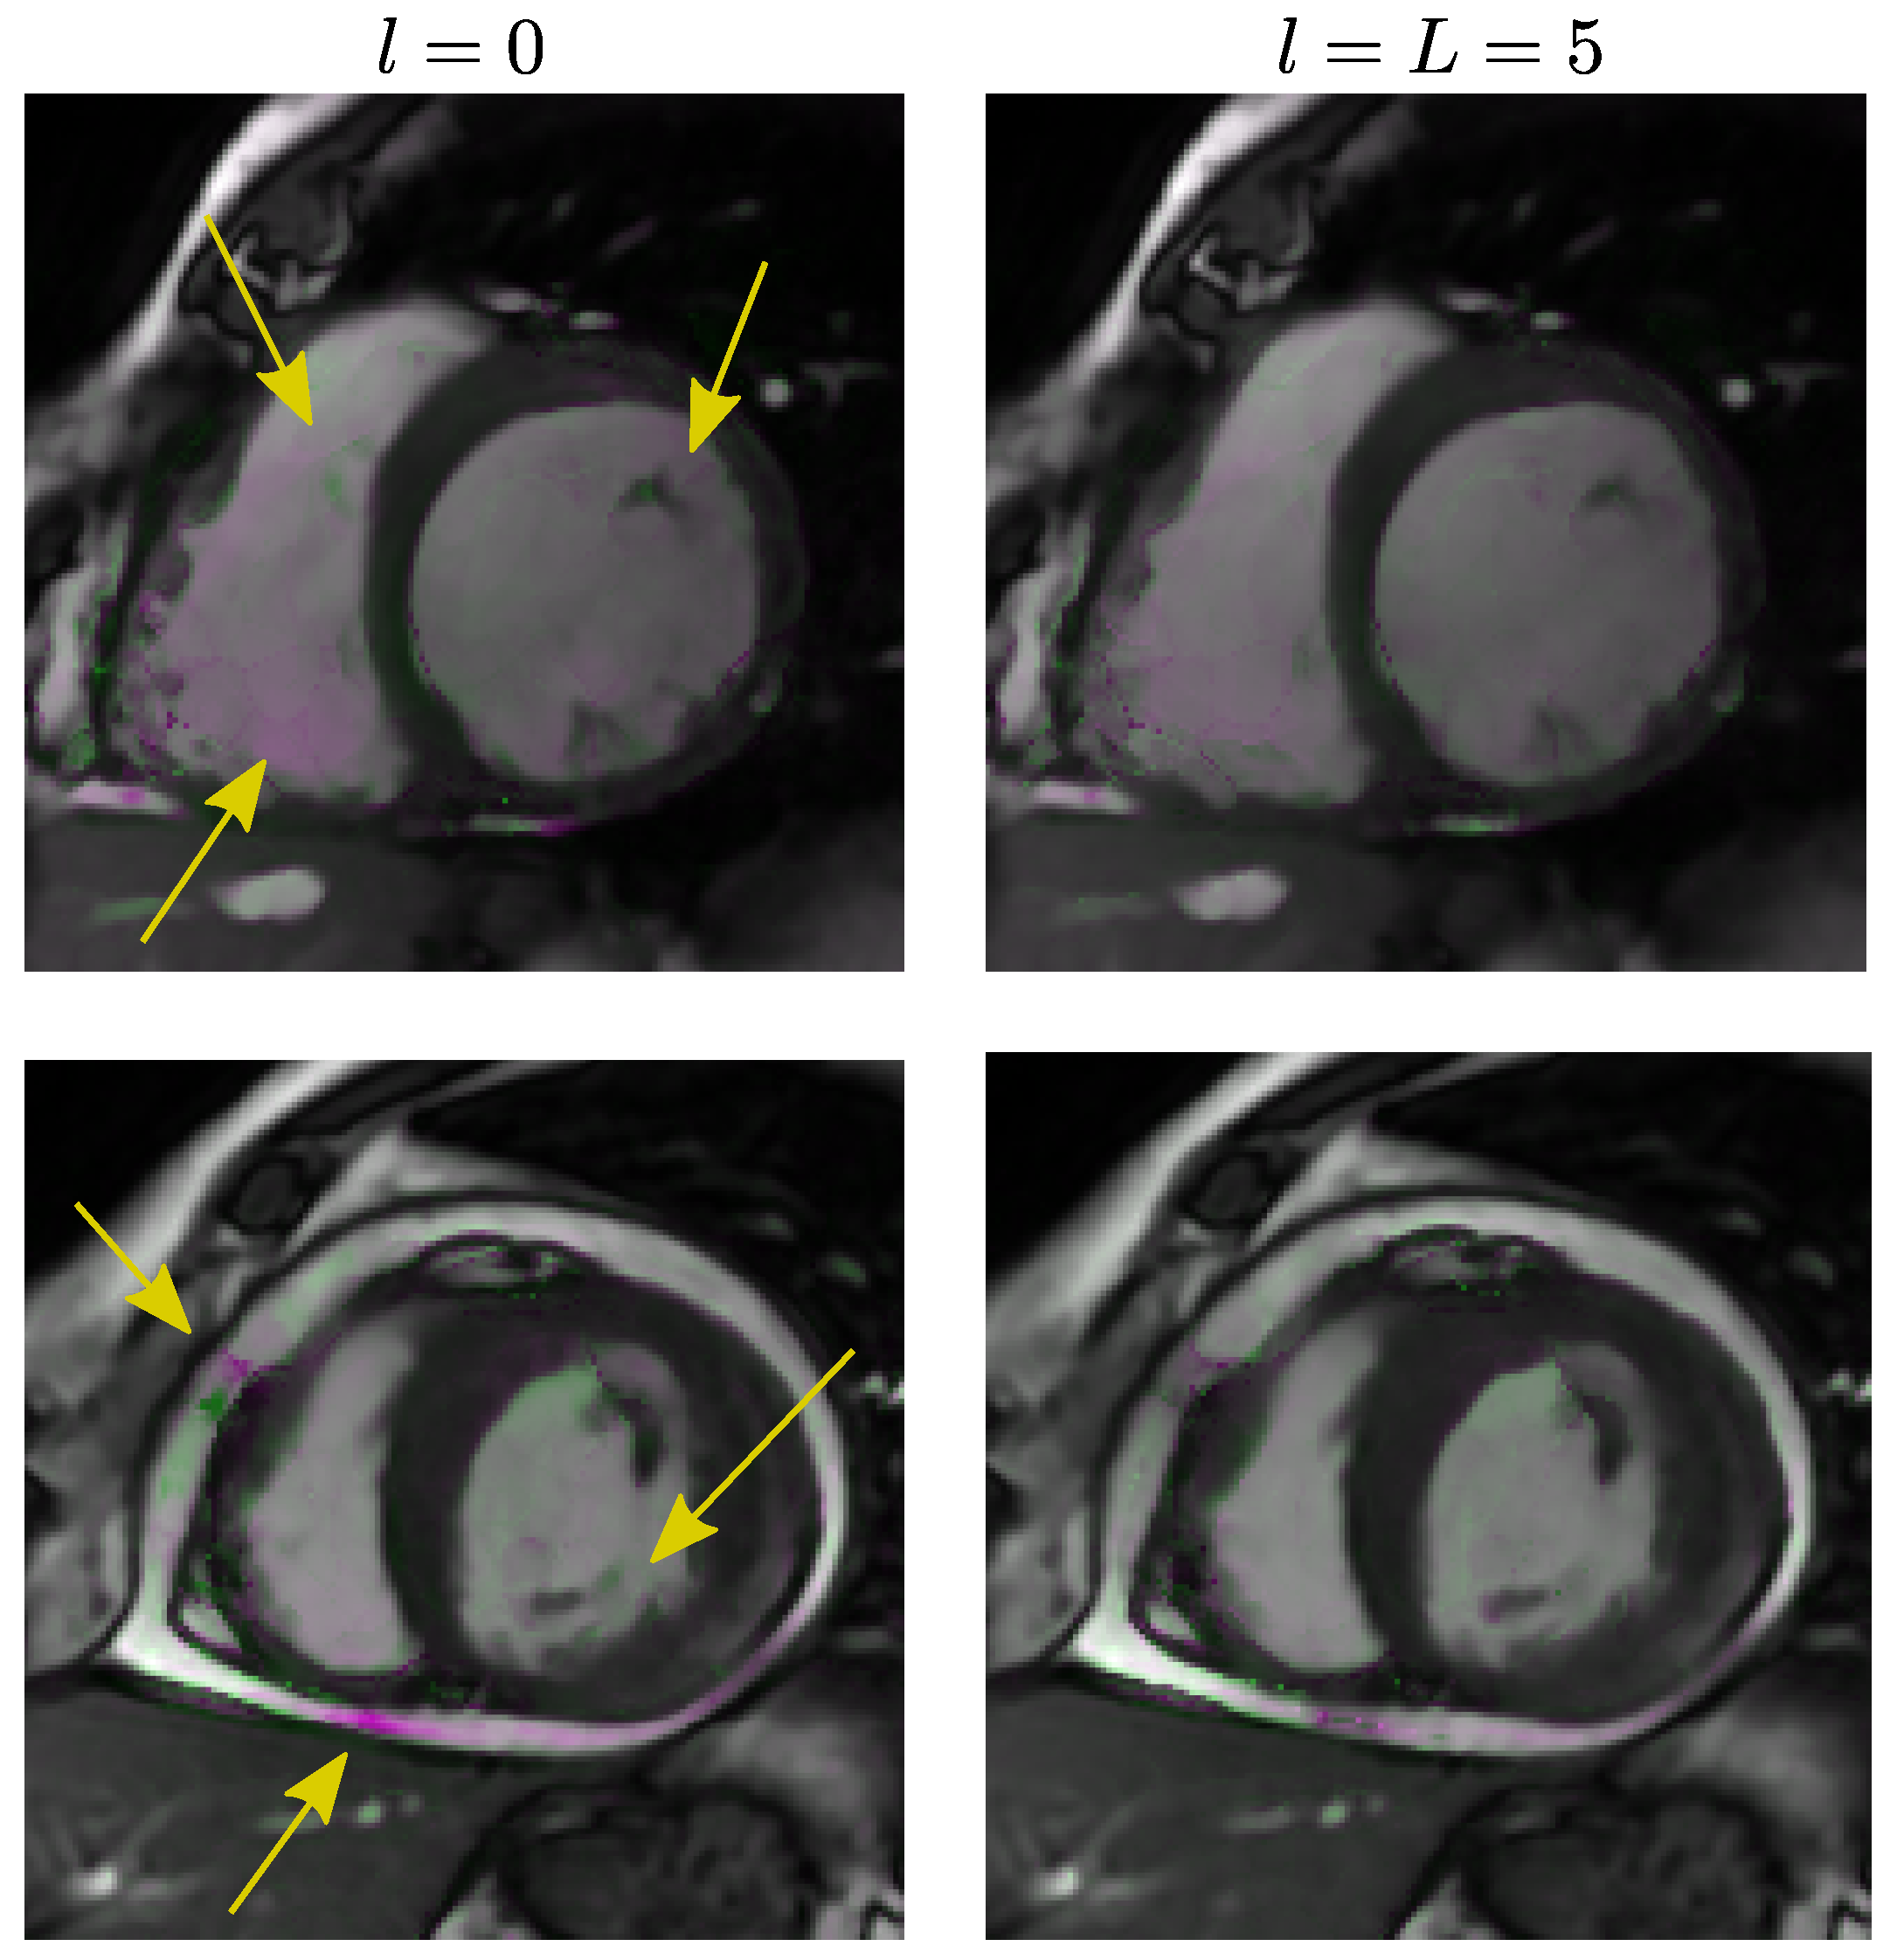

5.4. Results of Experiment 4